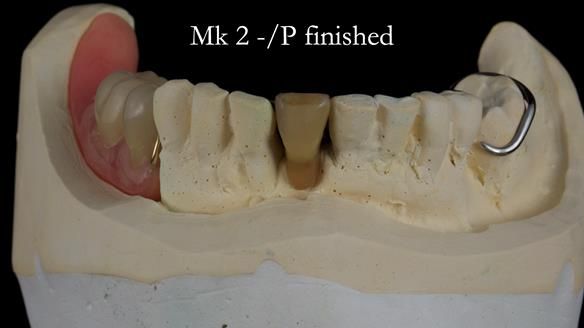

Welcome to my Newsletter 54 showing the making and fitting of dentures (a complete upper metal reinforced denture, a lower immediate partial denture and a definitive Scandinavian designed, metal based lower partial denture) for David, a 75 -year-old man. The full protocol workflow is presented including the use of dentate photographs to mimic his natural teeth.

The clinical situation and treatment process is shown in detail below. I provided the clinical work. Rowan Garstang, my dental technician, provided the technical work.

Interestingly we found that the upper complete denture when finished and fitted didn’t have good enough retention for David’s satisfaction. It was relined by adding compound to the buccal flanges – to almost overextend into the sulcus to ‘create’ a sulcus, followed by using a light bodied silicone impression material. This improved the function of the C/-considerably. A lower Scandinavian hygienically designed lower RPD was also provided which helped with occlusal stability and reseating the upper denture – further improving the fit.